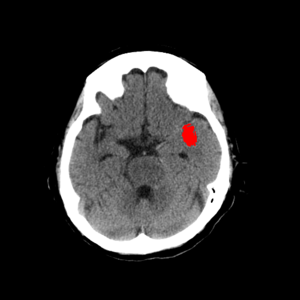

1-1. 高吸収領域の検出・表示例(下)

頭部CT検査において,周囲に比べ白く映る部分(高吸収領域)が見られる場合には,脳出血が疑われる。脳出血は高血圧・脳腫瘍・脳血管の異常などが要因となり,脳の動脈が破れて脳内部に出血した状態を指す。一方,周囲に比べ黒く映る部分(低吸収領域)が見られる場合には,脳梗塞が疑われる。脳梗塞は,脳内の血管が詰まるなどにより血液の流入が止まり,脳に酸素や栄養が行き渡らなくなる状態。また,急性期の脳梗塞では,頭部CT検査において,灰白質と白質の境界が消失するなどの所見(ECS=early CT sign)が見られ(2),こうした所見を見落とさずに治療につなげることが肝要である。